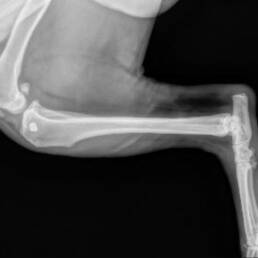

Rocky’s X‑rays told the truth before he could: three buckshot pellets lodged in his hips and hindquarters — and the vet warned there may be more hidden deeper in his body. Someone had shot him, then left him to suffer.

Soon after rescue, Rocky began limping badly on his right hind leg. The veterinary team discovered a torn ACL (Anterior Cruciate Ligament) and mild hip dysplasia on top of the buckshot wounds. During surgery, his torn ligament was repaired, the visible pellets were removed, and he was also neutered to prepare him for a brighter future.